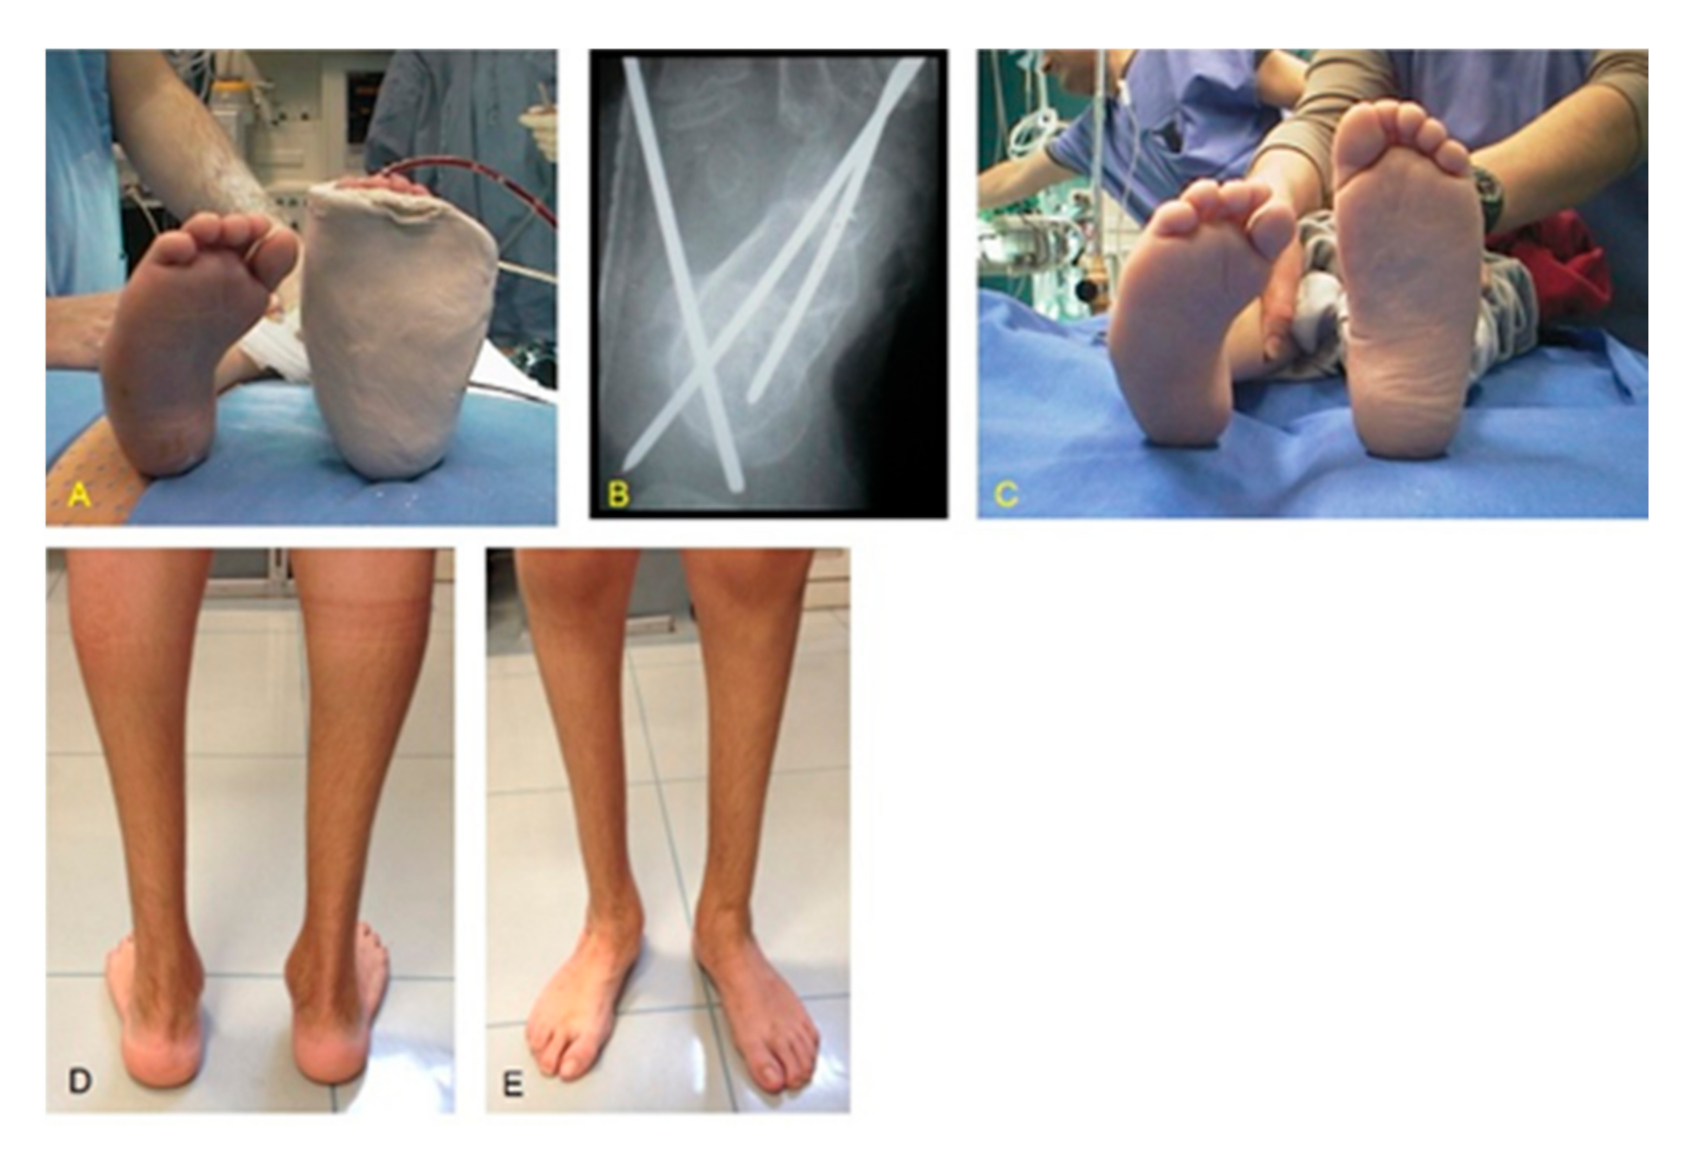

Figure 4. Same patient as shown in Figure 2: clinical aspects at long-term follow-up after 13.7 years. (A) Frontal view; (B) normal hind foot alignment; (C) Achilles tendon evaluation in tiptoes position.